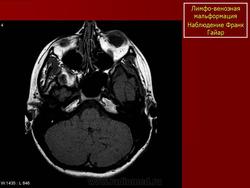

Лимфангиома орбиты (син.: сосудистая гамартома, венолимфатическая мальформация)

Врожденная доброкачественная сосудистая опухоль, которая состоит из расширенных сосудов, окруженных лимфатической тканью.

В большинстве случаев ограничивается конъюнктивой. Лимфангиомы орбиты прогрессивно увеличиваются в размерах, не склонны к спонтанной инволюции. В отличие от капиллярных гемангиом, которые часто подвергаются обратному развитию. Составляют менее 5% опухолей глазницы у детей. Могут сочетаться с лимфангиомами других локализаций. В норме в глазнице лимфатическая ткань не определяется.

Наиболее типичная черта: выявление уровней жидкости в образовании, за счет спонтанных кровотечений.

Экстраорбитальное (но может быть рапсоалагаться как в канале, так вне его), мультикистозное, мультифокальное объемное образование с неправильным контуром.

Гиперденсное, по плотности сопоставимо с мышечной тканью, негомогенной структуры образование, пересекает анатомические границы. Стенка лимфангиомы вариабельно накапливает КВ. Тип краевого накопления КВ иногда позволяет установить умеренное ремоделирование прилежащей кости. В структуре образования иногда определяются небольшие кальцинаты или флеболиты.